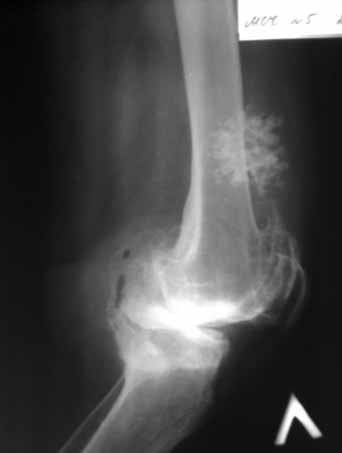

Пациентка 72 лет.Не обследовалась и не лечилась.

Работала поварихой до последнего времени.обратилась за медпомощью впервые.ходит без дополнительной опоры. Основные жалобы на ограничение движений и боли в правом коленном суставе.

Финансовые возможности ограничены.Чем можно помочь? Артродез? Протезирование?

Здравствуйте! А у вас нет ли R-гр? Для установления ст. артроза. Если же пациентка обращается первично, может стоит попробовать консервативное лечение?! НПВП, физиолечение, массаж, внутрисуставные блокады... Артродез и протезирование думаю всегда успеется.

однозначно протезирование

Больной несомненно показано эндопротезирование, однако случай не простой. Если у Вас нет достаточного опыта в проведении подобных операций, лучше направить больную в соответствующее лечебное

учреждение. По квоте.